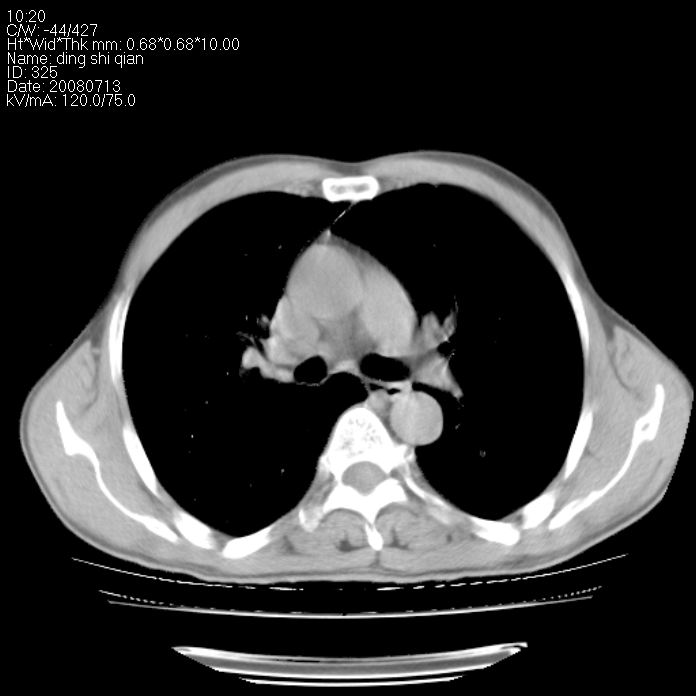

标题: CT14654:男 50岁 近来胸痛 [打印本页]

标题: CT14654:男 50岁 近来胸痛

右侧上肺块状软组织影,浅分叶,边缘毛刺证,与胸膜粘连,考虑:周围性肺癌

右肺上叶周围型肺癌可能性大。

右侧上肺块状软组织影,浅分叶,边缘毛刺证,与胸膜粘连,考虑:周围性肺癌!支持!

典型右肺周围型肺癌

首先考虑周围性肺癌,建议强化或穿刺明确

右肺上叶周围型肺癌。